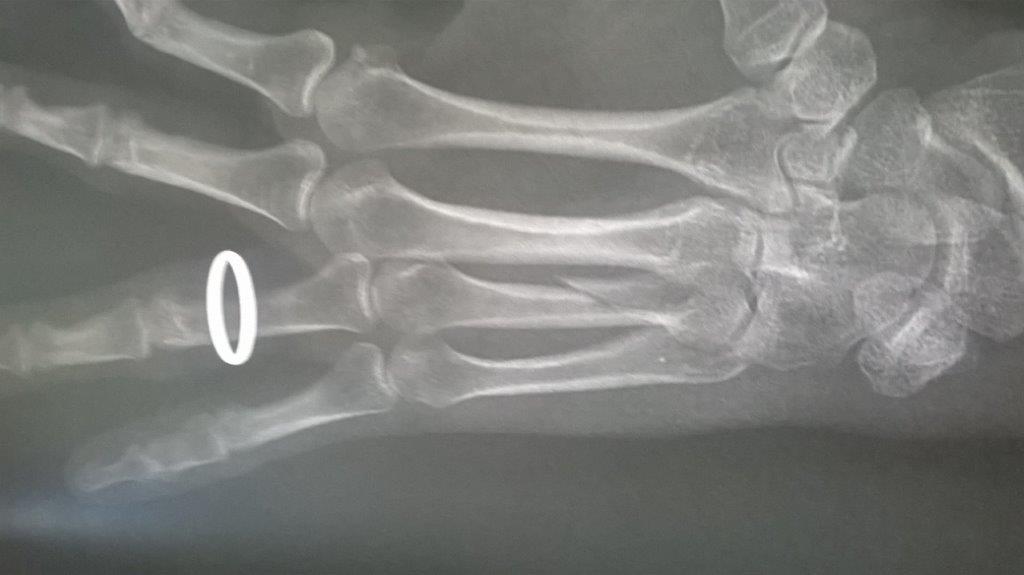

Résultat : fracture de la main gauche

Fichier(s) joint(s):

WP_20170914_001.jpg [ 47.5 Kio | Vu 29226 fois ]

Mais je confirme que ma saison de triathlon s'achève aujourd'hui. Main gauche immobilisé. Je suis au regret de déclarer forfait pour Paladru et d'abandonner les Mixirilliettes à leur triste sort